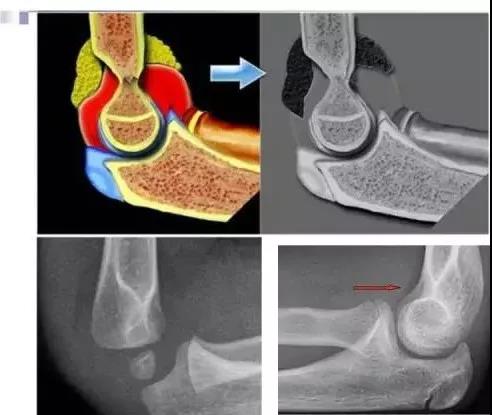

跌倒时肘关节处于过伸,从而造成髁上骨折,关节腔的积血导致脂肪垫移位,在平片上显示为八字征。

八字征(脂肪垫征):

骨折损伤周围组织,引起关节腔的积血,正常的脂肪组织向关节囊的外侧及上方移位,在平片上形成了八字征。

八字征在肘关节骨折的诊断中具有决定性的作用。

通常八字征阴性而又存在骨折的情况是不存在的。

如果八字征阳性,却没能够发现骨折,考虑是否存在隐匿性骨折,同样需要按未移位骨折来固定处理。

细微的骨折或折端没有移位,在平片上仅表现为八字征阳性;

Ⅰ型:包括青枝骨折和裂纹骨折,平片比较难发现,八字征阳性可能是唯一的发现。